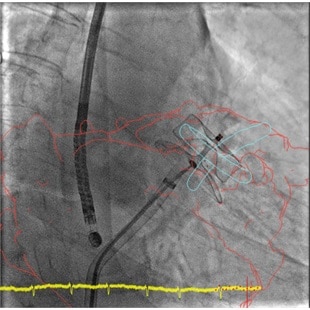

product-product-categories-Intervantional - 2016-valve_22.jpgКонтроль

Функция совмещения трехмерных изображений позволяет контролировать каждый этап, начиная с транссептальной пункции и заканчивая разверткой устройства. Существенно сокращает время процедуры, а также количество используемого контрастного вещества.